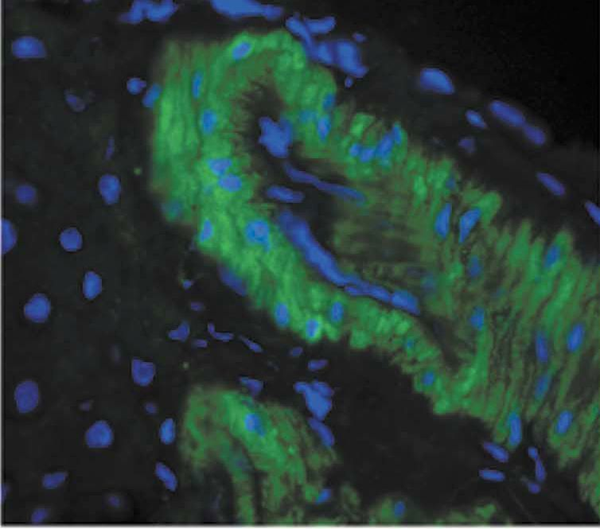

IHC (Immunohistochemistry)

(Immunohistochemistry analysis using Mouse Anti-Nitrotyrosine Monoclonal Antibody, Clone 39B6. Tissue: backskin. Species: Mouse. Fixation: Bouin's Fixative and paraffin-embedded. Primary Antibody: Mouse Anti-Nitrotyrosine Monoclonal Antibody at 1:100 for 1 hour at RT. Secondary Antibody: FITC Goat Anti-Mouse (green) at 1:50 for 1 hour at RT. Backskin obtained from transgenic mice.)